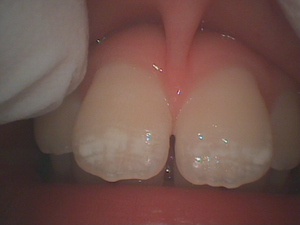

上顎の中切歯です。

切縁1/3が白濁しているのが観察できます。

これは歯が溶けた所を再石灰化した後で、口腔内にこのような白濁がたくさんあると

虫歯になりやすいという事が言えます。